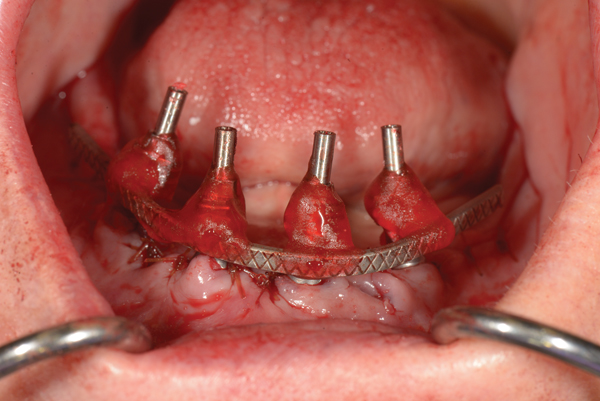

First-generation surgical protocols use the Maló guide, which is secured in a midline osteotomy after the malleable titanium band is bent to follow the arc of the opposing arch. Although, this guide aids posterior angled implant placements between 30° and 45°, it does not provide landmarks required for restoration-driven surgery. However, in the authors’ protocol, the provisional prosthesis guide provides the advantage of restoration-driven surgery not afforded by previous methods. Benefits of this include: visual verification of bone reduction, restoration-driven implant placement, and abutment orientation—all of which reduce chairtime and improve surgical accuracy and decision making (Figure 9). Once abutments and protective caps are secured, the soft tissues are carefully closed after circumferential adaptation of keratinized tissues.

Fig 9. Restoration-driven implant placement—Optimal implant position and distribution is achieved as a result of using the provisional prosthesis guide.

Figure 9